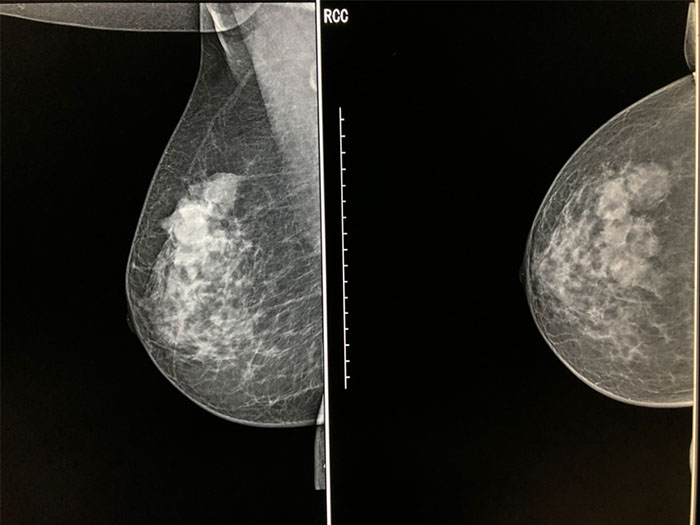

乳腺钼靶

案例

女性,57岁,检查发现右侧乳腺外上象限有多处肿物影。